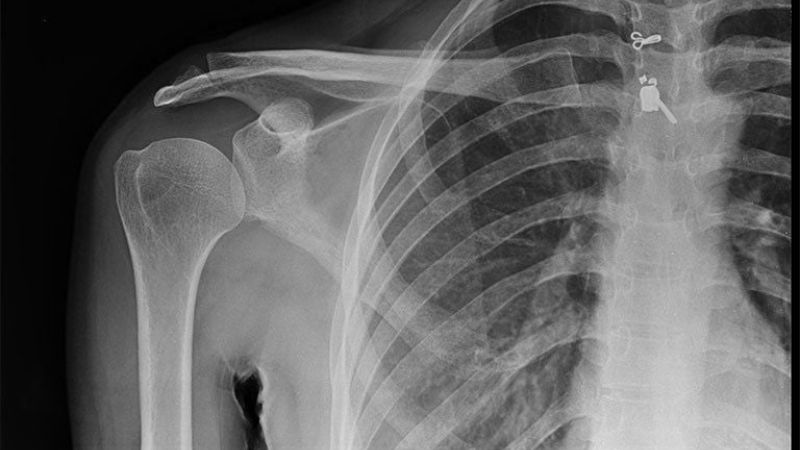

X - quang

X-quang là phương pháp được thực hiện để đánh giá bất thường các cấu trúc xung quanh khớp vai. Người bệnh sẽ được chụp tư thế xoay vai khoảng 30-45 độ để đánh giá chính xác. Mặc dù, không phát hiện được những dấu hiệu liên quan đến phần mềm nhưng X-quang sẽ cho cái nhìn tổn quan về khớp vai cũng như giúp phát hiện gai xương.

X-quang giúp đánh giá sơ bộ khớp vai